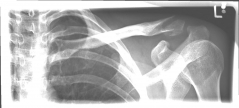

Picture 1: Displaced fracture of the left collarbone before surgery.